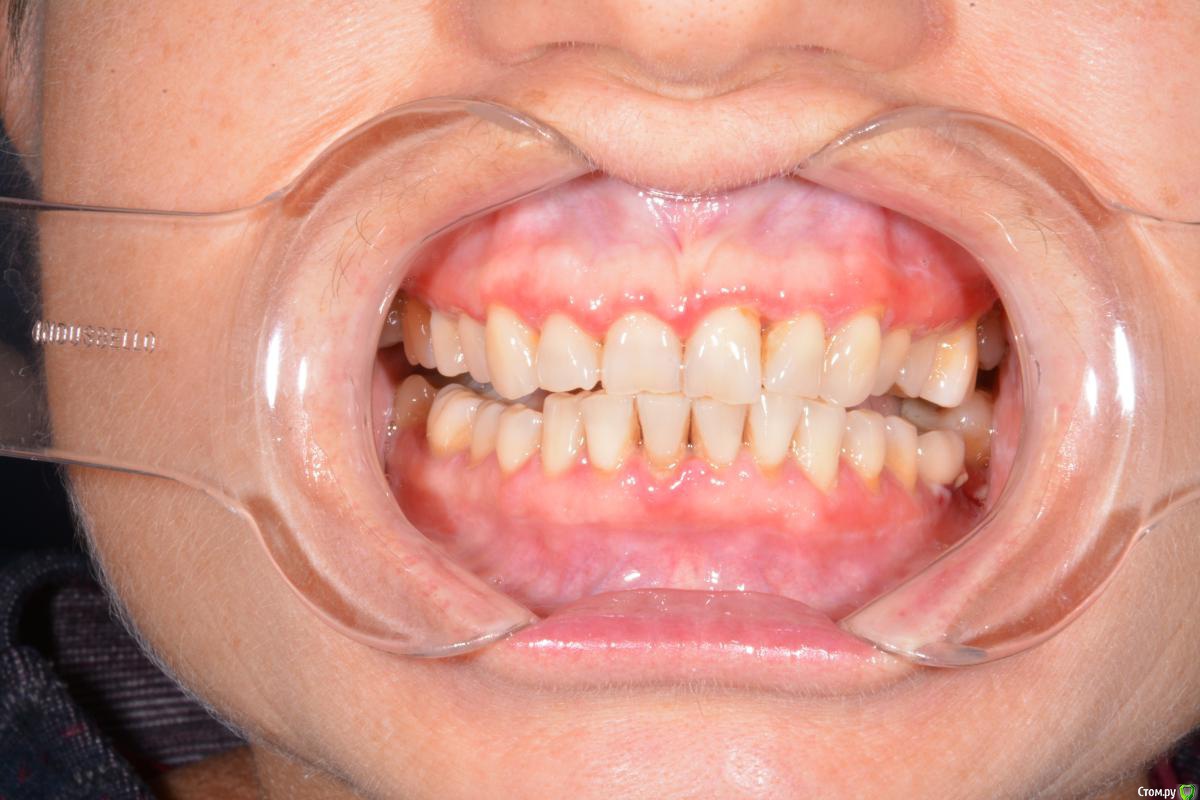

Руслан Аминов Опубликовано 6 ноября, 2019 Поделиться Опубликовано 6 ноября, 2019 Имплант Adin в области зуба 36, установлен в 2015 году. Шахта имплантата выходит язычно. Установлена коронка м/к на абатменте. Коронка расфиксировалась месяц назад, в клинику пациент не обращался. Сейчас десна гиперемирована, отечна, кровоточит при зондировании, при пальпации гноетечение. На Rg кость резорбировалась до 3 витка. На приеме почистили, помыли хг, коронку обработали и зафиксировали на временный цемент. Через неделю ситуация не улучшилась. Подскажите как снять воспаление. Имеет ли смысл проводить мягкотканную пластику? или удаление импланта? Ссылка на комментарий

red_butler Опубликовано 6 ноября, 2019 Поделиться Опубликовано 6 ноября, 2019 На приеме почистили что именно? ваши фото не информативны Ссылка на комментарий